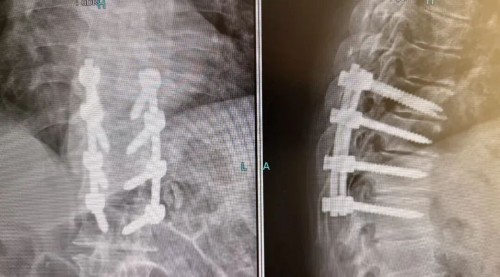

在麻醉科及护理团队的有力保障下,由韦竑宇主刀的骨科团队成功为老人实施了后入路胸椎管切开减压、植骨融合、椎弓根螺钉内固定术。

问题很可能不在颈椎,而在胸椎。吴迪做出这一关键判断后立刻为老人安排了紧急胸椎CT及核磁共振检查。结果印证了团队的精准预判:胸椎第10-11节段存在重度椎管狭窄,脊髓被严重压迫,这才是导致老人双腿瘫痪的真正“元凶”!